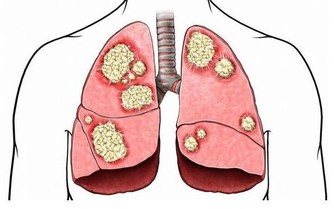

腿腳抽筋可能是因為動脈硬化:

動脈硬化是一種血管上的疾病,

在日常生活中,有很多的老年人認為抽筋是缺鈣,但是也要警惕動脈硬化的可能。

對於老年人來說,隨著年齡的增長,

如果不多加注意血管的健康,還長期吃高油脂高蛋白低纖維的食物,

無形當中就給血管增加了大量的油脂,

嚴重的就會出現下肢動脈硬化閉塞症,

也就是下肢動脈粥樣硬化斑塊造成的病症,這種病症在早期就有腿腳抽筋的症狀。